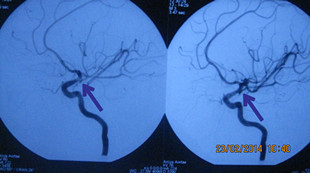

患者韦某某,女性,58岁,因“突发头痛头晕10小时”于2014年2月13日急诊入科,入院CT检查提示:自发性蛛网膜下腔出血。医生给予患者做全脑血管造影(DSA)提示:左侧颈内动脉后交通动脉瘤,大小约(3.0~4.0mm),并行动脉瘤血管内介入栓塞治疗,手术过程顺利,术后患者恢复良好,无神经功能障碍。

血管造影栓塞术前